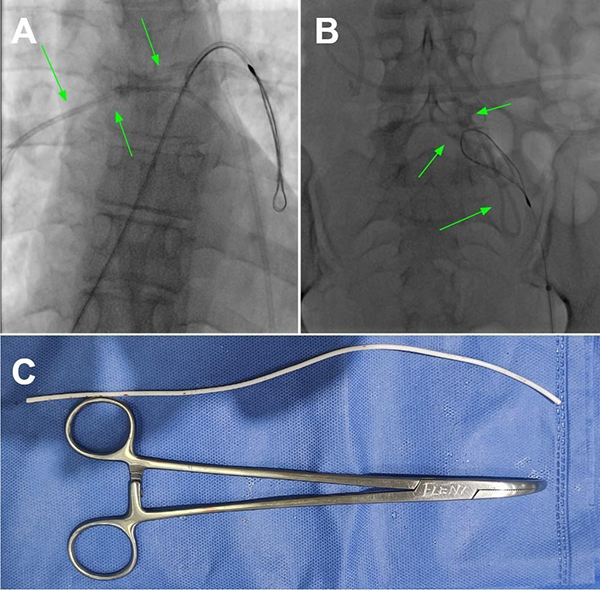

Tras 2 meses, la paciente volvió a consultar en guardia por náuseas, cefalea bifrontal con irradiación holocraneana de intensidad moderada y vómitos. Al examen físico se constató limitación de la mirada superior y colección líquida sobre herida craneal de derivación. Se realizó TC de cerebro con evidencia de ventriculomegalia y desconexión de catéter distal a la válvula (Figura 1). El estudio radiográfico reveló migración caudal del segmento distal del catéter al corazón (Figura 2). El segmento migrado fue rescatado mediante un abordaje endovascular transfemoral, en el cual se enroscó el catéter migrado con un catéter pigtail y se lo desplazó hasta la vena ilíaca primitiva izquierda para luego ser capturado a nivel ilíaco con un lazo trilobulado (Figura 3).

Figura 3. A. y B. Imágenes radioscópicas del procedimiento endovascular efectuado en el cuál se recupera y exterioriza el catéter distal migrado. C. Fotografía del catéter una vez retirado.